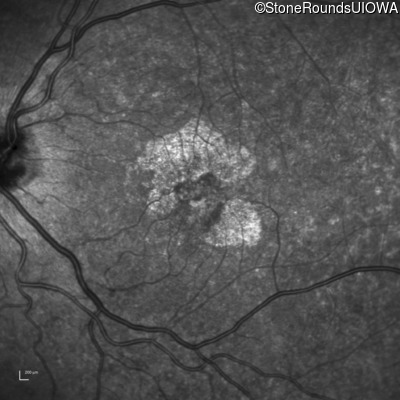

Blue Autofluorescence - Right - 20/32 +2

Exemplar